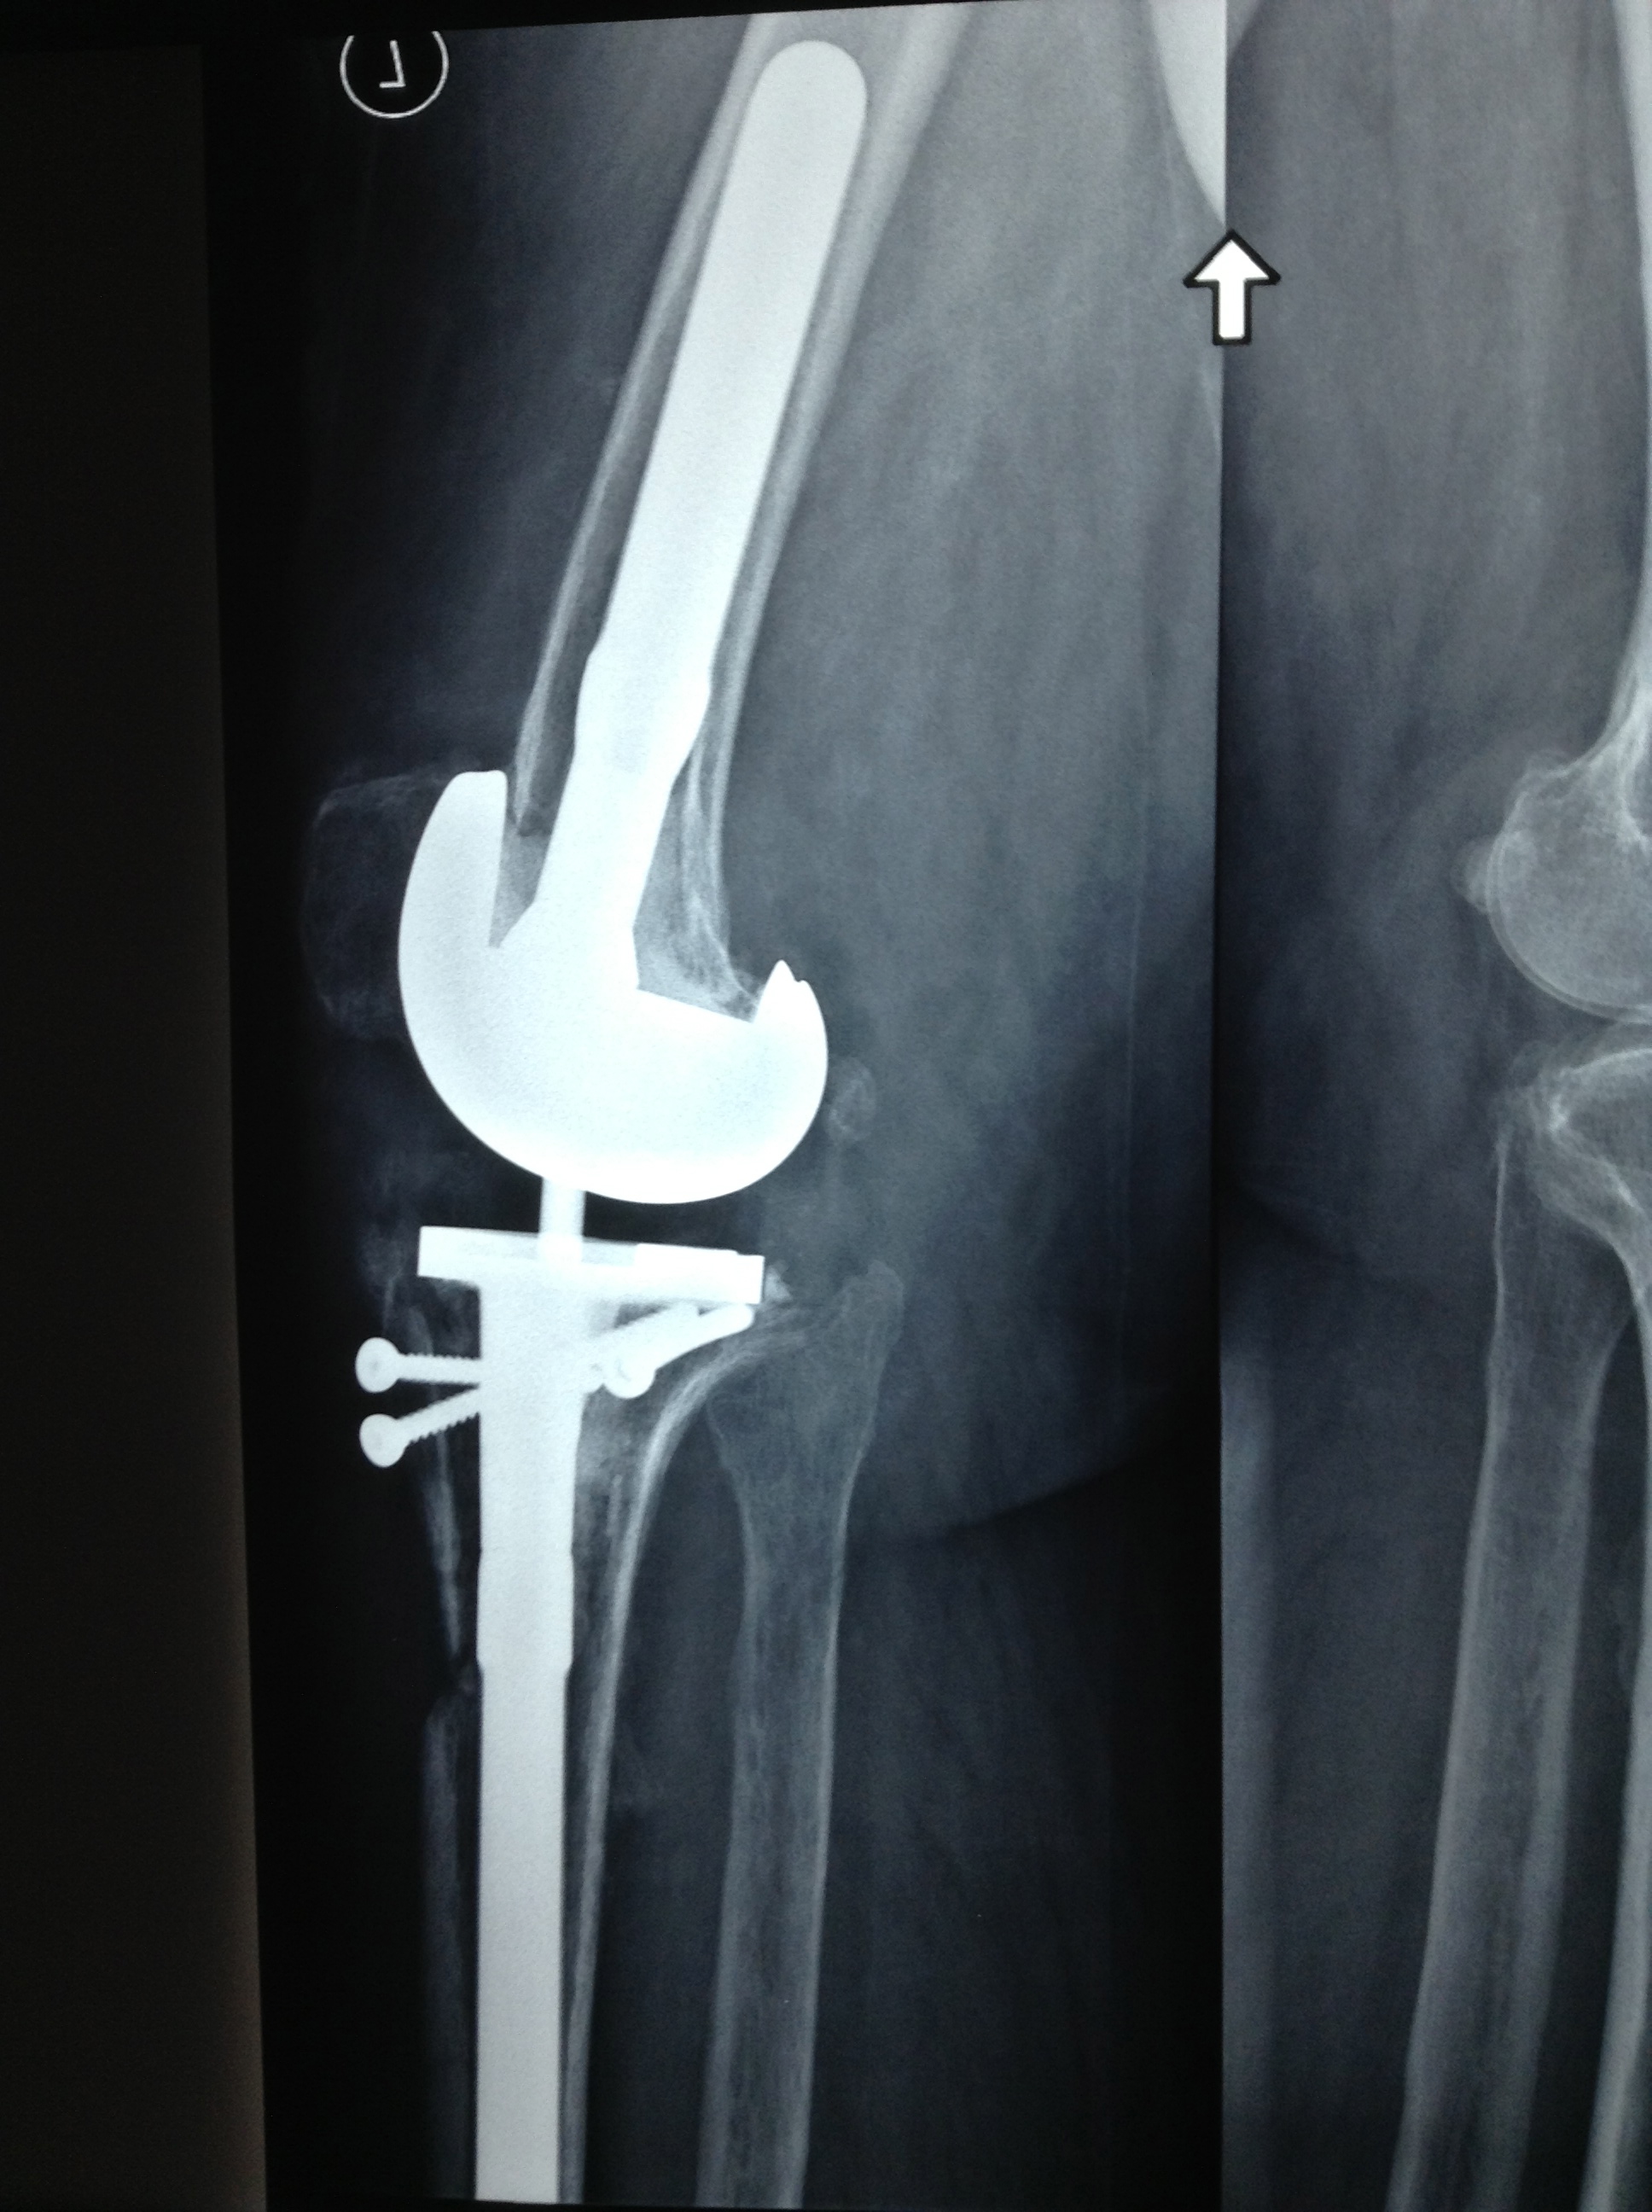

Revision Total Knee Replacement After Infection

• Revision Total Knee Replacement After Infection